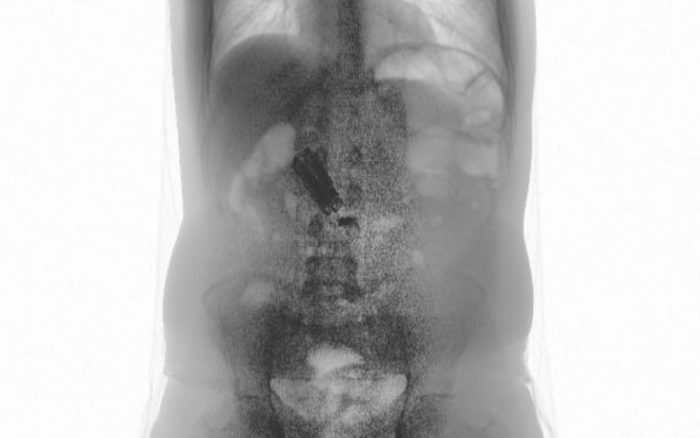

Um preso que cumpria pena no Centro de Progressão Penitenciária (CPP) de Jardinópolis, na região de Ribeirão Preto, foi flagrado pelo escâner corporal com um celular e um carregador em seu estômago. O caso ocorreu no último dia 20 de setembro após o detento retornar de uma “saidinha”.

De acordo com a Secretaria da Administração Penitenciária (SAP), pelo fato de ter ingerido o aparelho, o homem passou mal e precisou ser encaminhado ao pronto-socorro de Jardinópolis. No entanto, posteriormente, foi transferido até o Hospital das Clínicas (HC) de Ribeirão Preto, onde passou por cirurgia para a retirada do celular e do carregador.